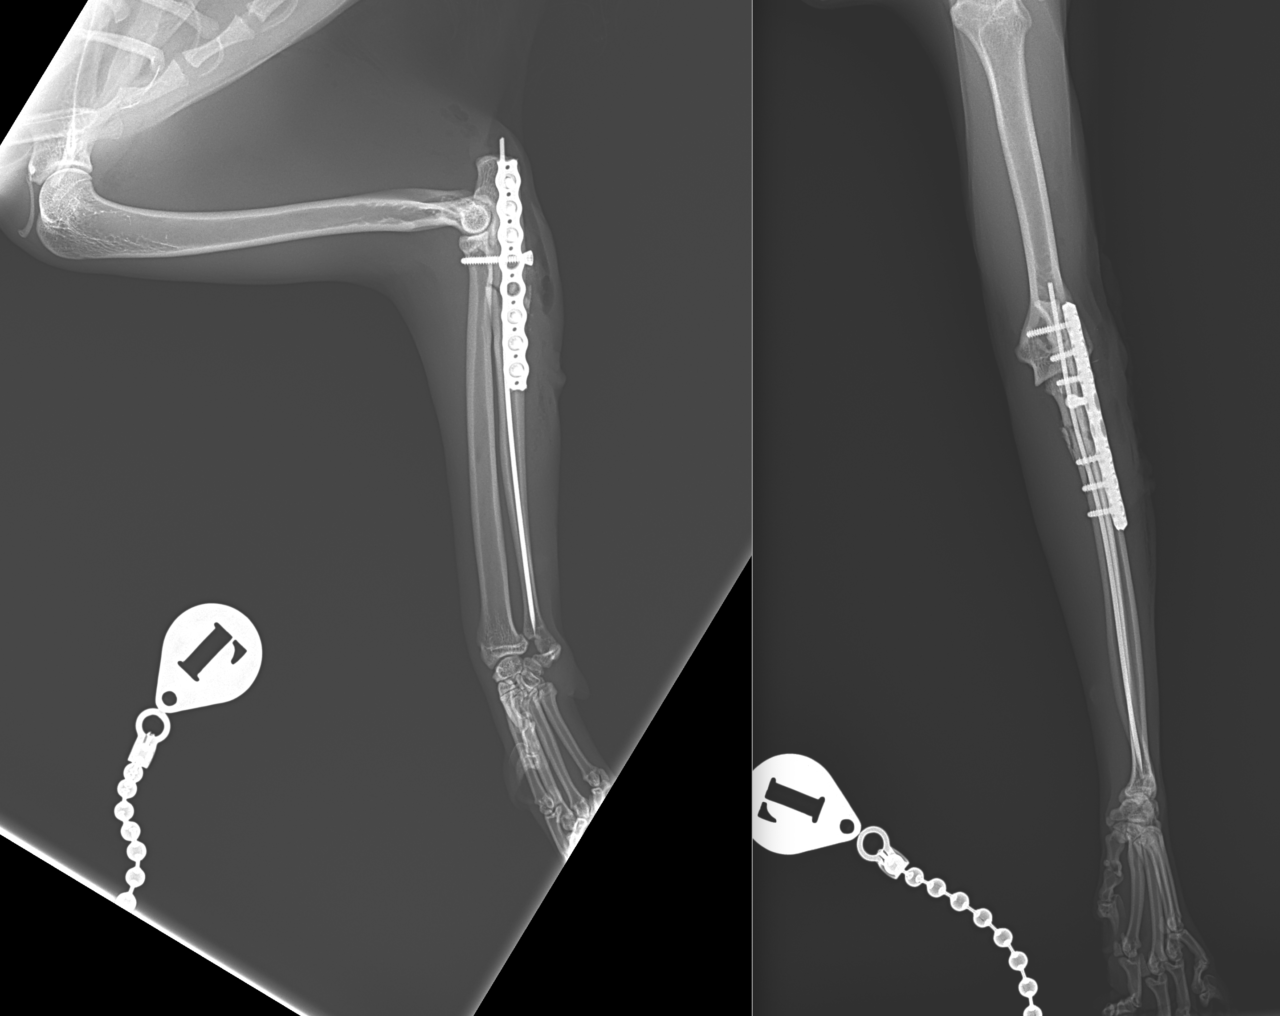

猫ちゃんがお家から居なくなり、探していたところお庭でうずくまって居るところを発見されました。かかりつけの動物病院で両側のモンテジア骨折と診断されました。(原因は落下事故と判明)外科的整復のため当院へ搬送されました。橈骨頭を整復したのち、尺骨にIM pinを刺入、2.0-Locking Plateで固定術を行いました。橈骨頭へ尺骨側からポジションスクリューで固定を併用します。このスクリューは約4週間を目安に抜釘を予定しています。